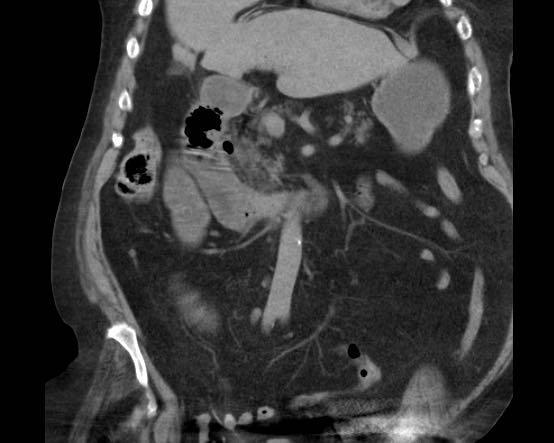

Đây là bệnh nhân có tình trạng ứ đọng dạ dày từng đợt và CRP thấp.

Cuộn qua các hình ảnh.

Các dấu hiệu hình ảnh là gì?

Một viên sỏi lớn bị “kẹt” trong đường rò từ túi mật biến dạng đến tá tràng.

Dày thành tá tràng thứ phát (đầu mũi tên) cùng mô viêm và mô xơ xung quanh gây ra tình trạng ứ đọng dạ dày từng đợt kèm nôn mửa.

Hình ảnh của một bệnh nhân nữ cao tuổi, nhập viện vì ứ đọng dạ dày và nôn mửa.

CRP là 55, nhưng được ghi nhận là 160 vài ngày trước đó.

Siêu âm cho thấy một viên sỏi lớn trong túi mật chứa đầy chất lắng cặn, thành túi mật không đều.

Dạ dày giãn to và có dày thành tá tràng đáng kể (đầu mũi tên) kèm viêm xung quanh (dấu hoa thị).

Nội soi dạ dày được thực hiện do nghi ngờ ác tính, nhưng sinh thiết chỉ cho thấy hình ảnh viêm.

Tiếp tục xem CT.

CT xác nhận chẩn đoán hội chứng Bouveret.

Dẫn lưu túi mật qua da đã giải quyết các triệu chứng ứ đọng dạ dày.

Một năm sau, viên sỏi dường như đã tự di chuyển vào lòng tá tràng, và bệnh nhân phát triển tắc ruột do sỏi mật điển hình, được phẫu thuật thành công.